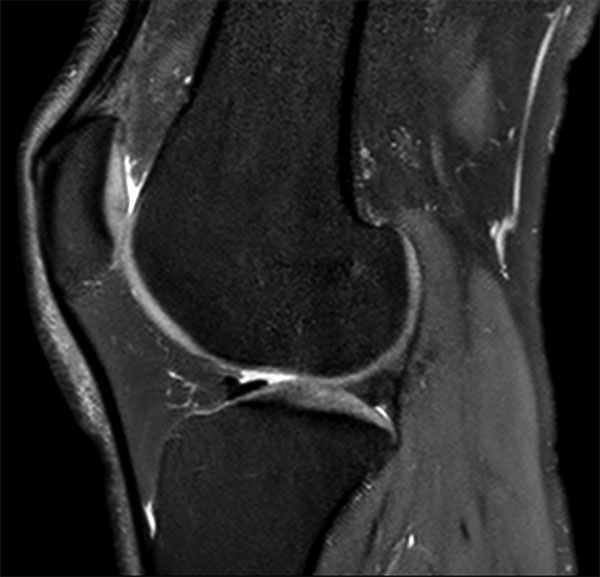

Comprehensive 3D knee imaging with MSK VIEW